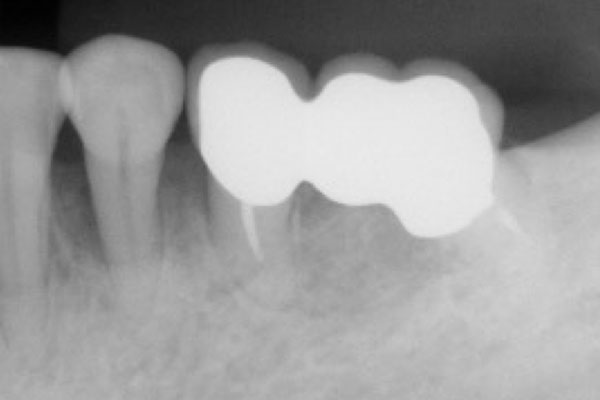

歯周病は、あごの骨を溶かす病気です。病状は歯肉の中で進行します。骨の様子を確認するため、当院では「CT」を使って検査します。

CTはレントゲンと同じくX線を用いた検査装置です。360度回転して撮影するので、あらゆる方向からの透過映像を立体的に確認でき、2次元のレントゲンより詳しく病状を把握できます。